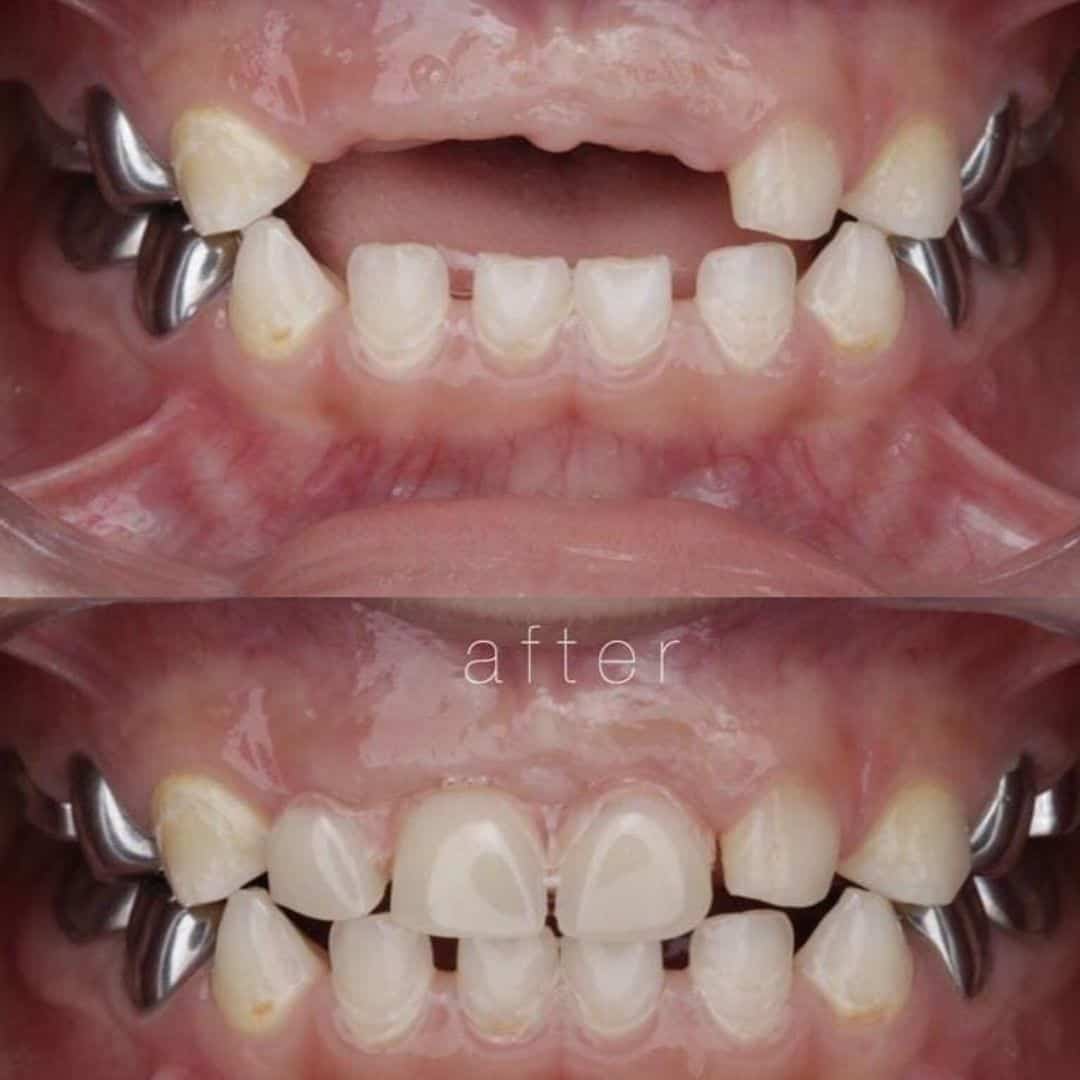

نتائج رائعة لمراجعينا